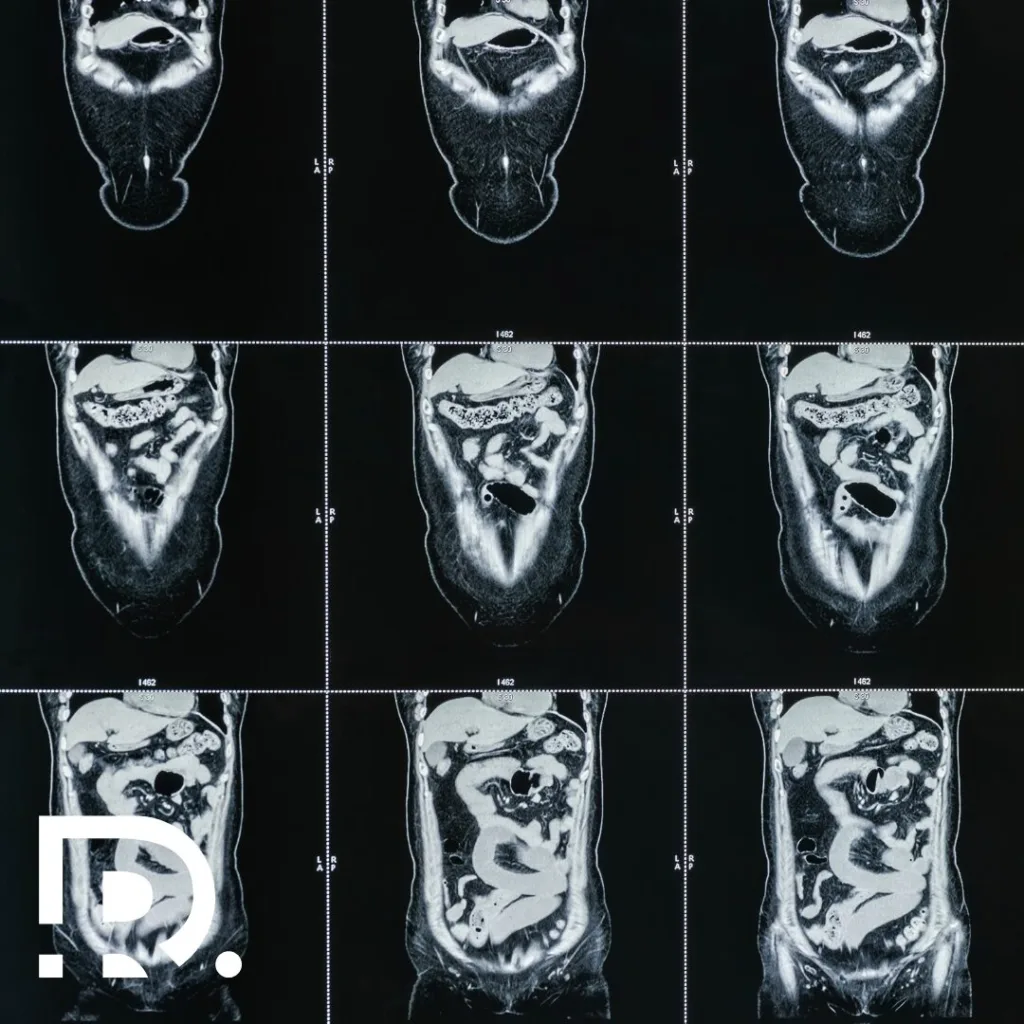

Chirurgia robotică este cea mai modernă tehnică de chirurgie minim-invazivă ce permite chirurgului să facă intervenții chirurgicale cu un grad înalt de complexitate folosind incizii foarte mici (de 1-2 cm).

Cu experiență vastă și abilități avansate, sunt specializat într-o gamă largă de intervenții chirurgicale, incluzând chirurgia herniilor, chirurgia generală și minim-invazivă, chirurgia oncologică și chirurgia endocrină. Sunt aici pentru a te ajuta să găsești cea mai bună soluție medicală pentru nevoile tale